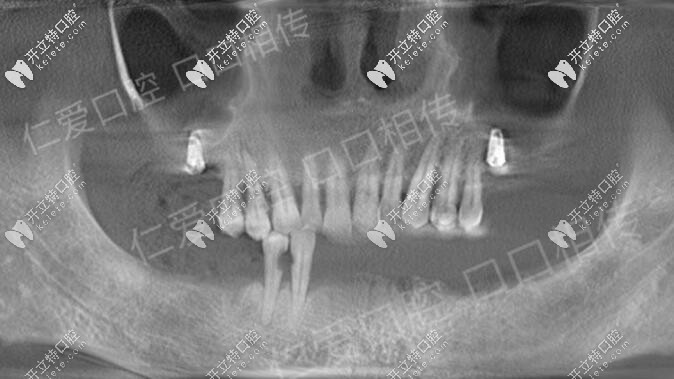

諾貝爾ALL-ON-6即刻負(fù)重種植牙馬上有牙,武漢人都來(lái)這種牙

諾貝爾即刻種植即刻負(fù)重種植牙,無(wú)牙頜顧客的福音,ALL-ON-6即刻負(fù)重,植入6顆種植體就可種出整排牙。